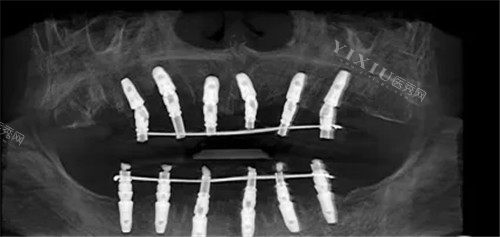

三、半口/全口种植牙:29900元起,当天种牙当天用

半口即刻负重种植牙:29900元起(含4颗种植体+桥冠)

All-on-4半口种植:44500元起(适合牙槽骨萎缩患者)

全口即刻负重种植牙:149999元起(当天戴牙,吃饭不耽误)

技术优势:

即刻负重技术:通过倾斜植入种植体,减少手术创伤,缩短愈合周期。

个性化桥冠设计:根据患者牙弓形态定制桥冠,美观度与咀嚼力兼备。